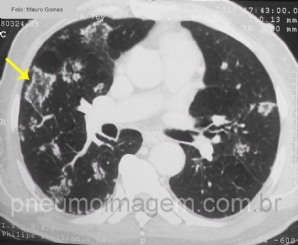

CASO CLÍNICO #33

Nem tudo é o que parece ser. Muitas vezes a tuberculose não aparece sozinha e, sim, associada a outras doenças, como neste caso. Qual a sua hipótese para a imagem? Deixe os seus comentários abaixo. ***** Not everything is what seems. Many times TB is not an ...